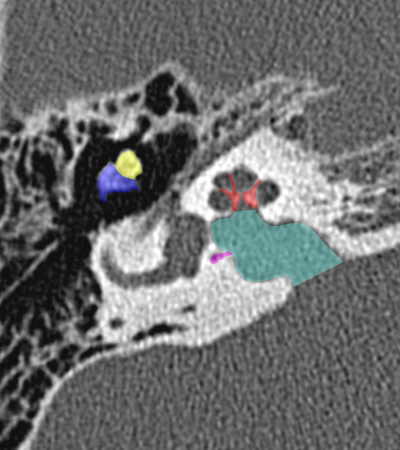

Radioanatomie du rocher sur coupes TDM

Différentes coupes de référence (A. Attyé 2013)

Coupe axiale passant par le canal semi-circulaire supérieur Coupe axiale passant par le canal semi-circulaire latéral Coupe axiale passant par le modiolus de la cochlée Coupe axiale passant par la fenêtre ronde Coupe axiale passant par le ganglion géniculé Coupe axiale passant par l'articulation incudo-malléaire Coupe axiale passant par la partie pétreuse de l'artère carotide interne Coupe axiale passant par le nerf tympanique

Coupe axiale passant par le foramen styloïde Coupe coronale passant par le muscle tenseur du tympan Coupe coronale passant par le recessus epitympanique Coupe sagittale passant par le segment mastoïdien du nerf facial coupe sagitalle oblique passant par le canal semi-circulaire supérieur (plan de Pöschl) Reconstruction axiale passant par le plan de l'étrier Coupe axiale passant par les apex pétreux